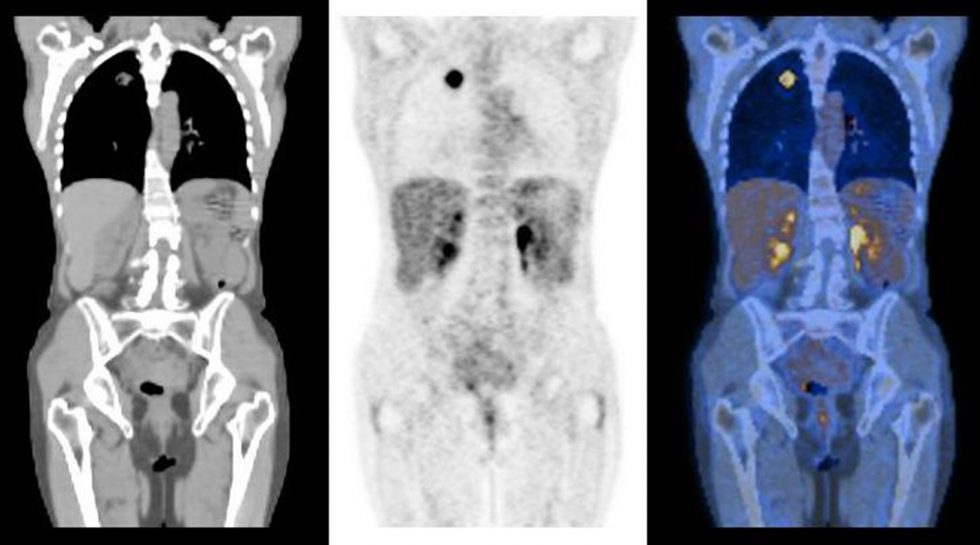

L'imagerie moléculaire regroupe des techniques d'imagerie ou des associations de différentes techniques permettant de visualiser, in vivo :

- des appareils capables de voir au travers du corps (rayon X, ultra-sons, infrarouge, tomographie…). Dans certains cas, l'épaisseur des tissus à traverser par l'imageur n'est plus limitante (c'est le cas pour les traceurs radioactifs émettant des photons à 511 keV, qui sont faiblement atténués par le tissu et permettent une précision femtomolaire) ;

- des marqueurs, sondes ou traceurs, de natures diverses (colorants, produit de contraste, marqueur radioactifs ou opaques au rayons X, émulsion fluorescente telle que la sentidye, des protéines fluorescentes éventuellement produites in situ par l'organisme, après qu'il a été génétiquement modifiée (souris de laboratoire par exemple).

Ces produits (injectés ou ingérés ou produits par un organisme génétiquement modifié pour cela) visent un organe, un type de cellule, ou une molécule particulière qui sera ainsi mise en évidence par l'imagerie.

- rendre visibles in vivo certaines macromolécules, des protéines ou de l'ADN ou d'autres molécules d'intérêt (via des marqueurs spécialisés) ;

Il est ainsi souvent possible (quand le cancer est en surface ou juste sous la paroi d'un organe, ce qui est souvent le cas) de nettement différencier (par des couleurs différentes) les parties saines et tumorales d'un organe en cours de cancérisation, ce qui permettra au cancérologue et au chirurgien d'affiner le diagnostic puis ou de limiter l'exérèse au strict nécessaire ou de mieux cibler un traitement par rayonnement. Pour l'instant l'observation en direct sur l'organe vivant durant l'opération n'est pas possible, mais c'est une des pistes explorées par l'imagerie moléculaire ; - observer l'effet de certains pathogènes ;

- L'utilisation combinée de plusieurs modes d'imagerie devrait permettre de par exemple produire des images mieux corrigées (pour la diffusion du rayonnement dans les tissus, le bruit, etc.) et éventuellement en 3D et animées, et de bien meilleure qualité encore, avec une méta-information enrichie pour chaque pixel de l'image : à chaque pixel peuvent être associées des informations de température, nature moléculaire, état, etc.